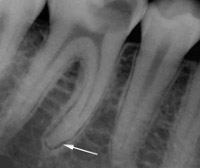

Постановка диагноза фиброзный периодонтит основывается на жалобах пациента, результатах клинического осмотра, рентгенографии, ЭОД, термопробы. При физикальном обследовании клинические признаки воспаления отсутствуют: вертикальная перкуссия причинного зуба отрицательная, слизистая вокруг верхушек корней без изменений. Во время препарирования эмалево-дентинной границы при зондировании устьев каналов пациент боли не ощущает. Решающими в диагностике заболевания являются данные прицельного рентгенологического исследования. Расширение периодонтальной щели в участке верхушечной трети или на всем протяжении корня свидетельствует о развитии фиброзного периодонтита.